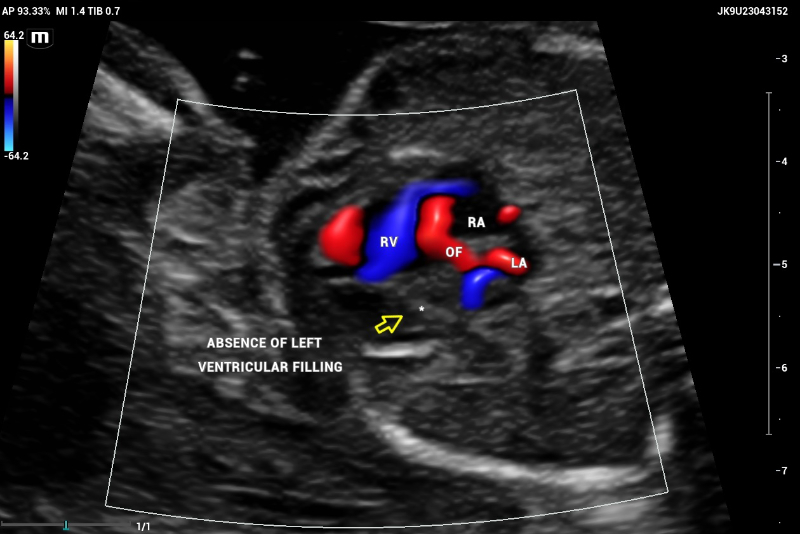

The emergence of the aorta was difficult to visualize, and hypoplasia or aortic atresia was suspected during the exam. Color and power Doppler were used to visualize systolic and diastolic flow to obtain ventricular filling images. Absent color Doppler could be visualized by entering the LV through the mitral valve(Figure 9), in contrast to a normal echocardiography showing normal filling and size of symmetric ventricles.

CASE Fetal echocardiography. Absent color Doppler could be visualized by entering the left ventricle (arrow) through the mitral valve. Right ventricle (RV) with normal filling. Oval foramen with left-right shunt. Ultrasound compatible findings with Hypoplastic left heart syndrome (HLHS)

Figure 9. CASE Fetal echocardiography. Absent color Doppler could be visualized by entering the left ventricle (arrow) through the mitral valve. Right ventricle (RV) with normal filling. Oval foramen with left-right shunt. Ultrasound compatible findings with Hypoplastic left heart syndrome (HLHS).